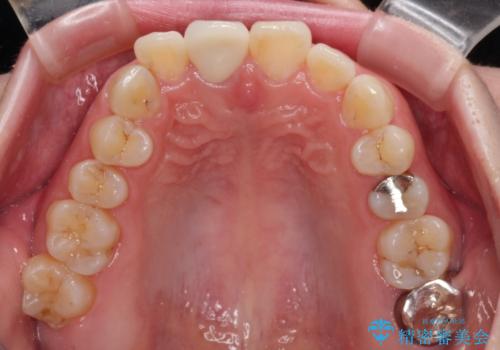

根管治療された状態に大きな問題はなかったため、土台を植立し、オールセラミッククラウンにて補綴治療を行うこととしました。

オーダーメイドタイプのクラウンを選択されたため、周辺の歯と調和が取れる色合いとなるまで修正を繰り返しました。